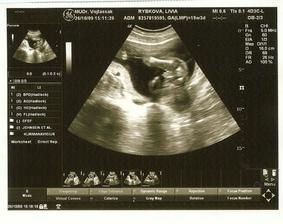

livike

19. aug 2009

My a náš prvý očakávaný anjelik

Po roku dlhého skúšania sa nám konečne podarilo...Sme s manželom veľmi šťastní a nevieme sa našeho prvo-rodeného bábatka dočkať.